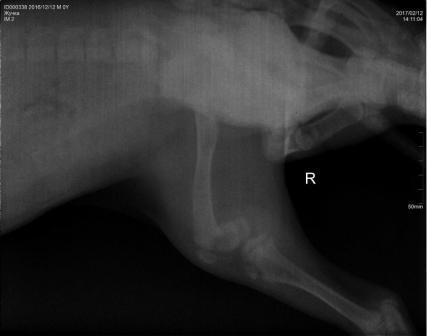

12.02.2017г. к воротам подкинули коробку с щенком (сука). У щенка перелом обеих задних лап. Правая - перелом в области коленной чашечки, левая лапа - перелом в области бедренной кости и коленной чашечки. Ей необходима операция! Стоимость операции 10500р. Необходимую сумму нужно собрать в течении недели, щенок не может ходить и жить полноценной жизнью...

Прием щенка осуществлял специалист хирург-ортопед из Москвы (Ветеринарный центр МЕДВЕТ). Оперировать будем в ЛПВЦ ПеСиКоТ г. Петушки, здесь же и делали рентген. Телефон для связи: 8-919-021-43-91 Мария